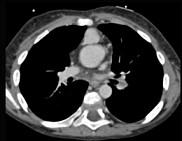

问题 患者,男性,8岁,发绀、气促,易感冒,彩超提示只见一个心室,CT检查如图所示,请选择正确的选项 ( )

选项 A、考虑三尖瓣狭窄 B、右前斜位示左心房增大,心后上缘后突压迫冲钡食管 C、左前斜位示心影向后下方突出 D、考虑二尖瓣狭窄

答案 BCD